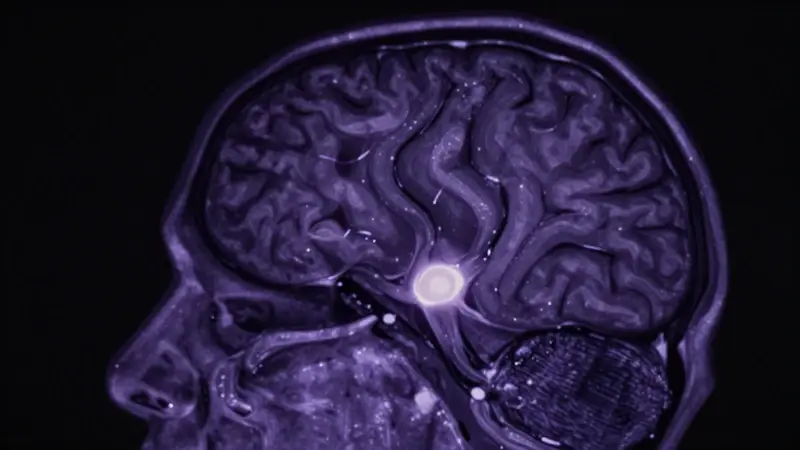

Escaneo cerebral con brillo etéreo mostrando la glándula pineal, representada como un centro bioluminiscente, sobre un fondo de resonancia magnética.

Escáner cerebral realista mostrando la glándula pineal iluminada en tonos azulados y violáceos, dentro de una máquina de resonancia magnética.

La glándula pineal, a menudo llamada la “epífisis”, es una pequeña glándula con forma de piña ubicada en el centro del cerebro. Aunque pequeña, su impacto en nuestra fisiología es enorme. Se encarga de sintetizar y secretar melatonina, la hormona que regula el ciclo sueño-vigilia. Su ubicación en el cerebro la hace especialmente sensible a los cambios en la luz percibidos a través de los ojos, aunque no sea directamente sensible a la luz como ocurre en algunos animales.

Escáner cerebral humano con la glándula pineal resaltada y brillante en una sala de resonancia magnética oscura.

Resonancia magnética de un cerebro humano con la glándula pineal resaltada en tonos violetas y azules, evocando un ambiente de sueño profundo y misterio.